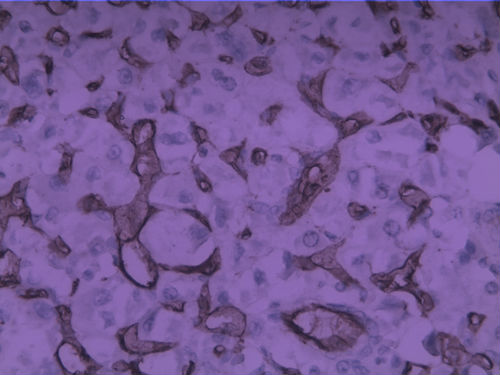

女30Y,大腿肿物5Y,直径3cm

腺泡状软组织肉瘤

首选腺泡状软组织肉瘤

考虑血管源性恶性肿瘤,图中看到肿瘤样血管结构,腔内见红细胞

CK,S100,HMB45均阴,Ki67 4%,